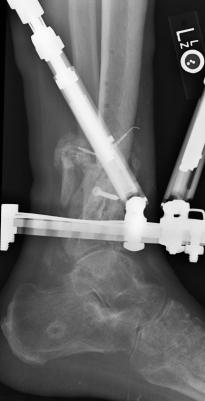

Postoperative (14th) images of left ankle

The image(s) displayed here were created following Liam's 14th surgery which was performed by Dr. Saunders. It was thought that the bones

in the ankle had fused, but during surgery it was discovered that the ankle was a total non-union. The halo frame was removed and 3 anchors were

placed on the tibia. Also added to the ankle was all available Medtronic Infuse material (rhBMP). One image may provide proof that Dr. Saunders

is possessed. ;-) The first set of x-ray shots were taken 3 weeks after the 14th surgery. The 3 new claw anchors are visible as seen through

the cast. Excess bone debris was also removed. Some of the photos had to be taking with the cell phone since the main camera failed. The last

x-rays show that some of the screws in the claw anchors are backing their way out of the leg. The next phone photos show that a screw from a

claw anchor was actually sticking out of the leg and could easily be removed (by hand) by the doctor. The very last photo is of the leg wrapped

in a black cast. Black was used to signify the loss that was soon going to occur. :-(